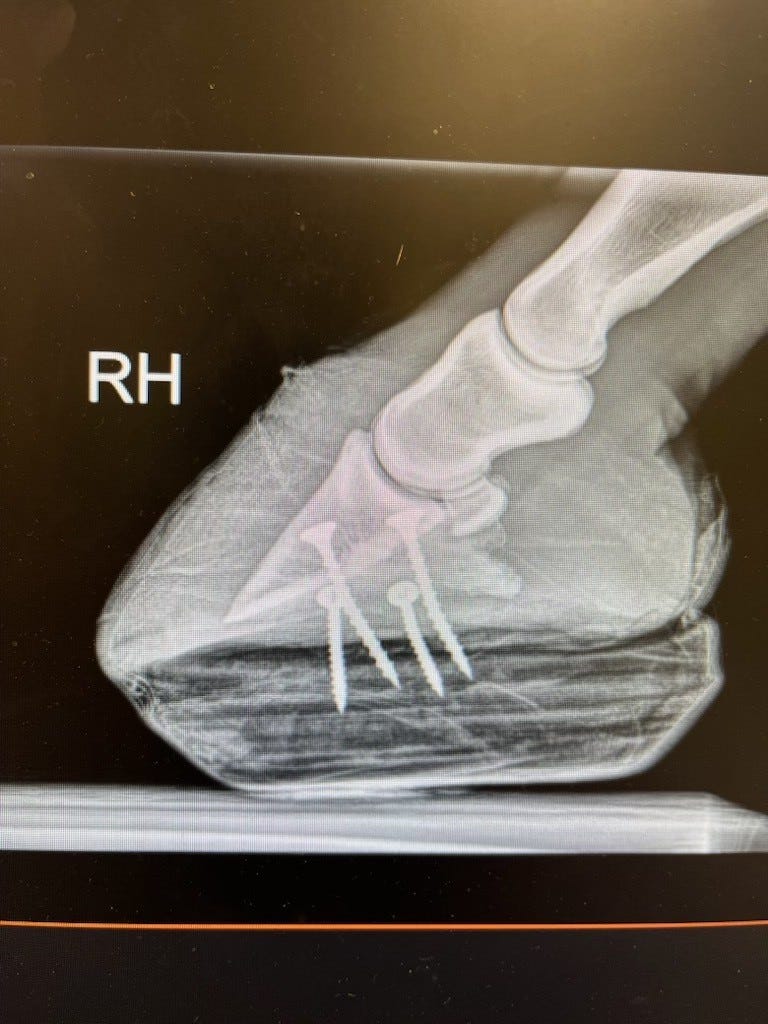

Her x-rays were - mixed. The implants on the surgery leg still appear to be in place, which is good. It's the right leg - the "good" leg - that is bearing too much weight. The coffin bone is far too close to the sole (and that is from the inside). If it breaks through under the strain of the extra weight, this is over.

The biggest concern is that her support limb — the “good” leg — may be struggling under that load, potentially developing laminitis. She is wearing a wooden clog to help support that foot, but it also limits what we can directly evaluate.